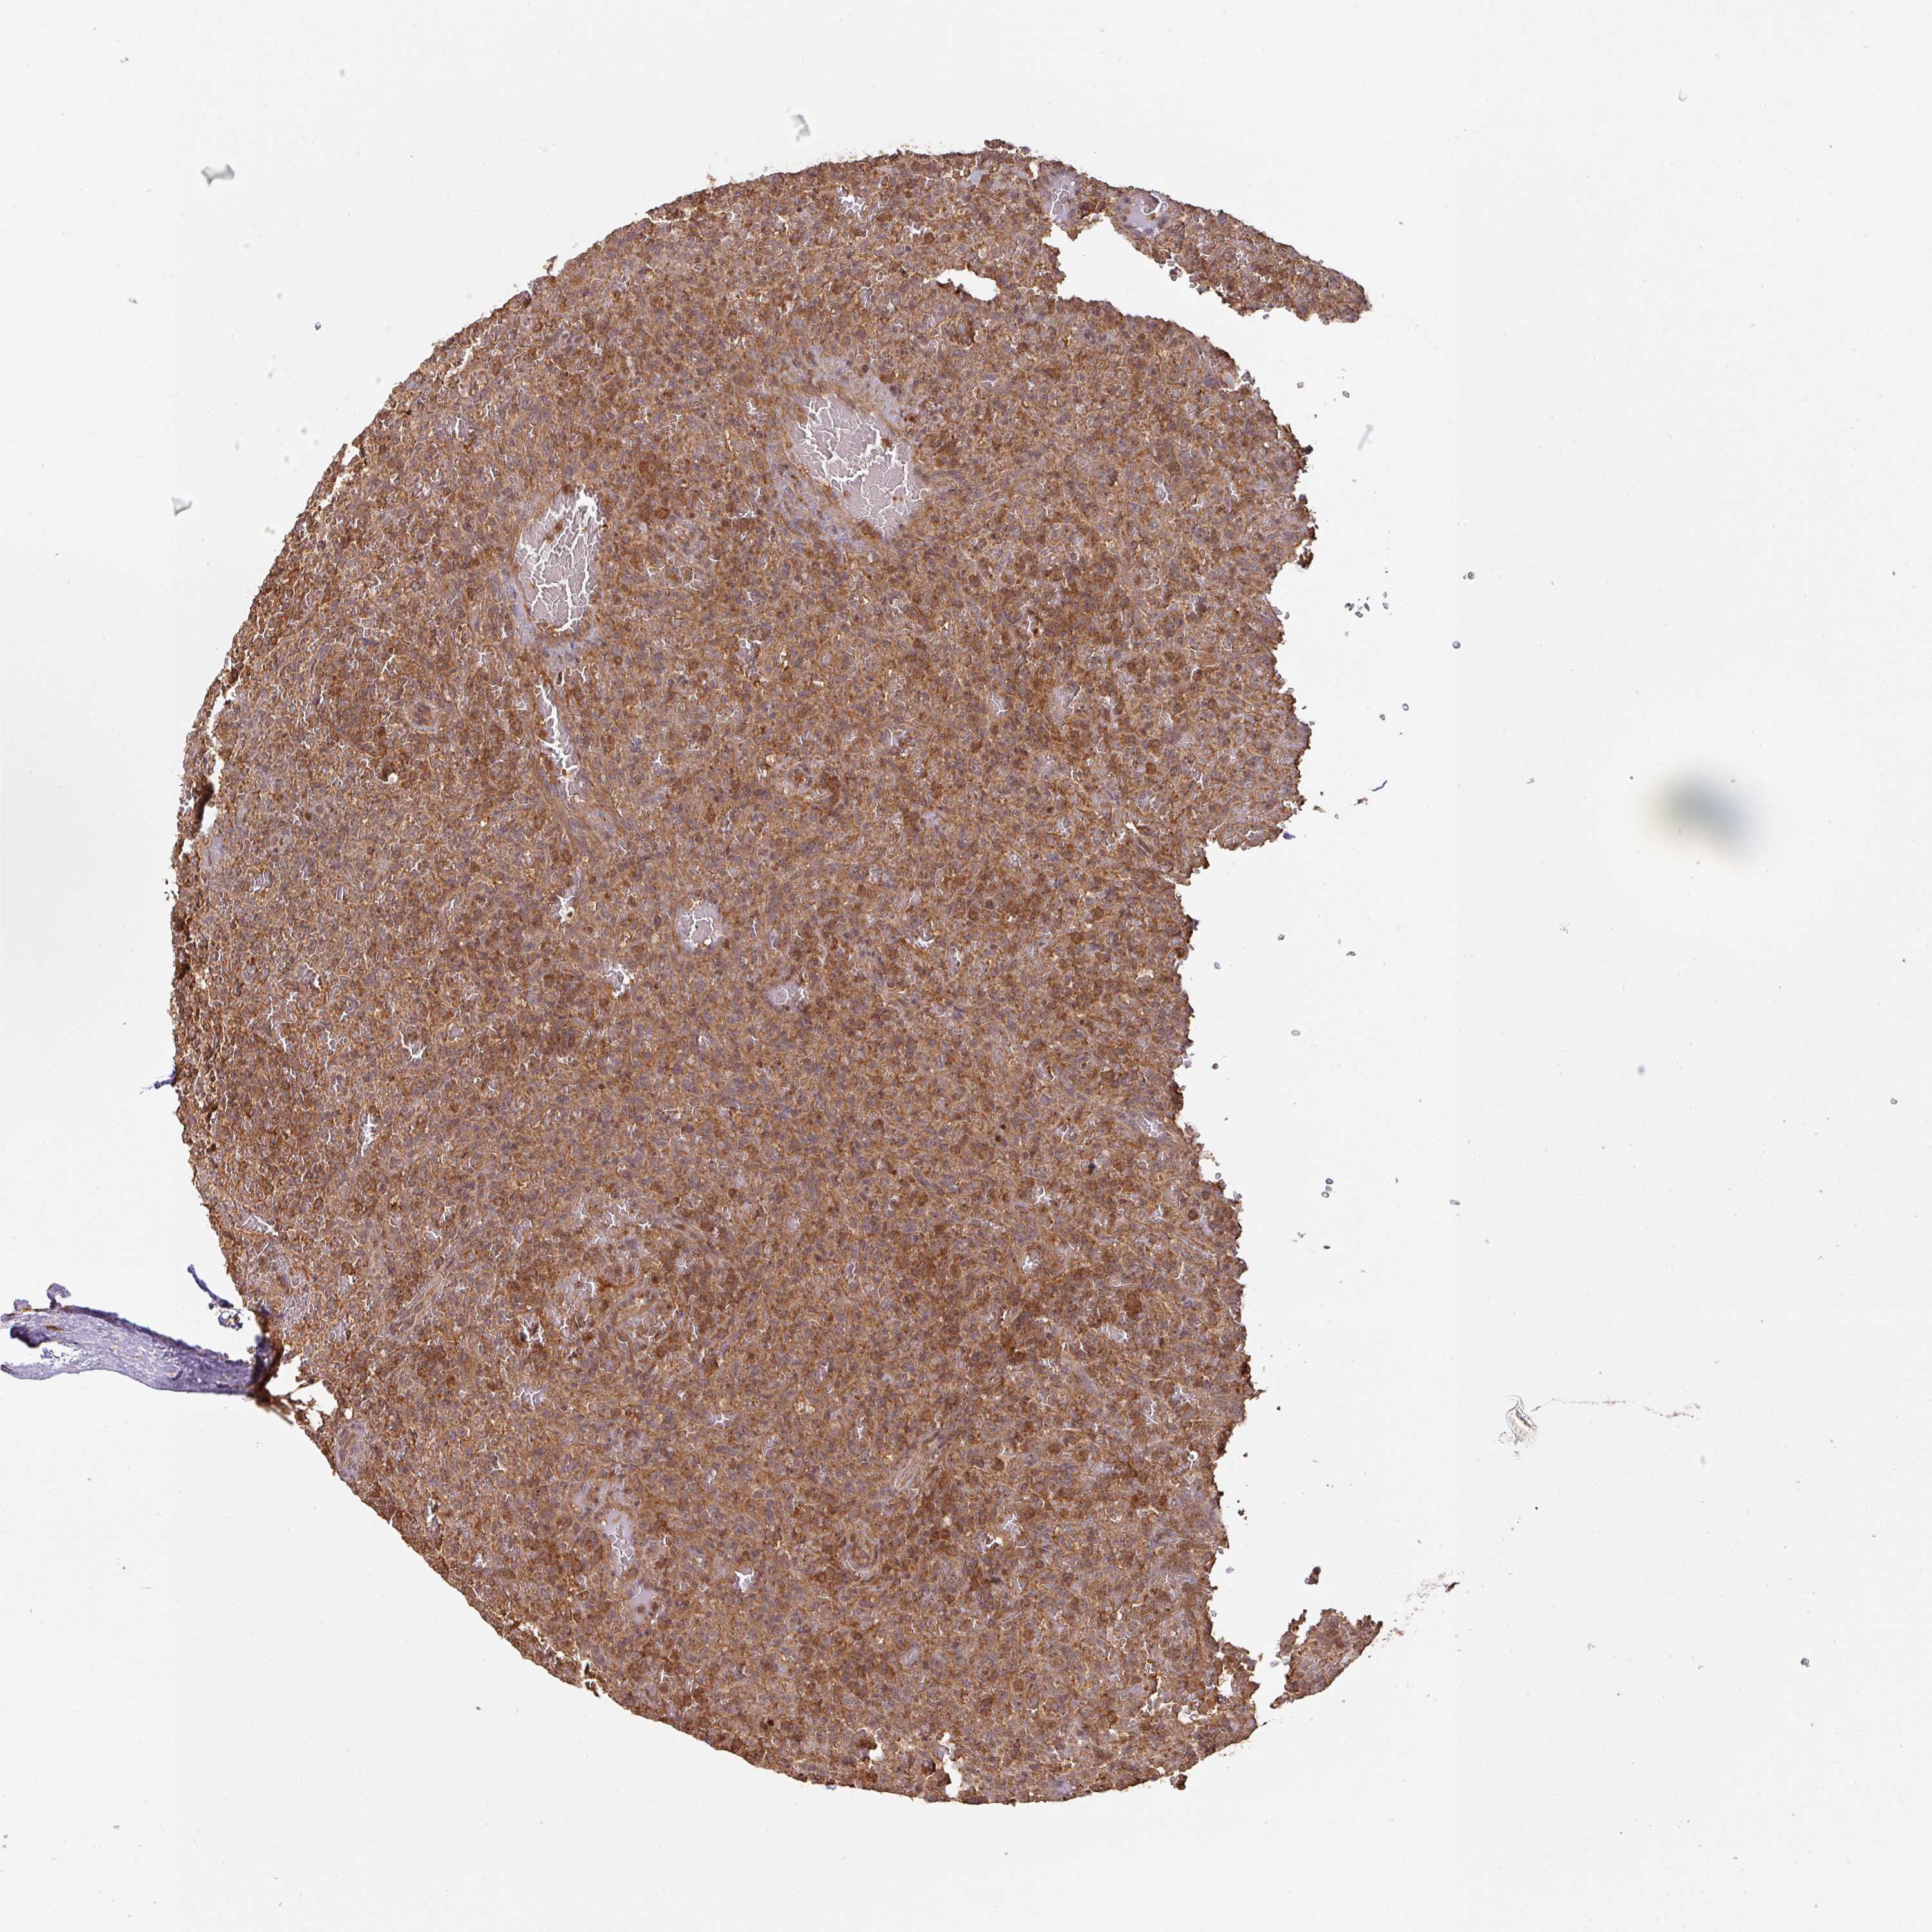

LYMPHOMA - Protein expressioni

A mouse-over function shows sample information and annotation data. Click on an image to view it in a full screen mode. Samples can be filtered based on level of antibody staining by selecting one or several of the following categories: high, medium, low and not detected. The assay and annotation is described here.

Antibody staining in the annotated cell types in the current human tissue is reported as not detected, low, medium, or high, based on conventional immunohistochemistry profiling in selected tissues. This score is based on the combination of the staining intensity and fraction of stained cells.

Each image is clickable and will lead to virtual microscopy that enables deeper exploration of all samples and also displays staining intensity scores, fraction scores and subcellular localization as well as patient and tissue information for each sample.

Antibody HPA043161

Antibody HPA046692

Staining

High

Medium

Low

Not detected

Intensity

Strong

Moderate

Weak

Negative

Quantity

>75%

75%-25%

<25%

None

Location

Nuclear

Cytoplasmic/membranous

Cytoplasmic/membranous,nuclear

Malignant lymphoma, non-Hodgkin's type, Low grade

Malignant lymphoma, non-Hodgkin's type, High grade

Hodgkin's disease, NOS